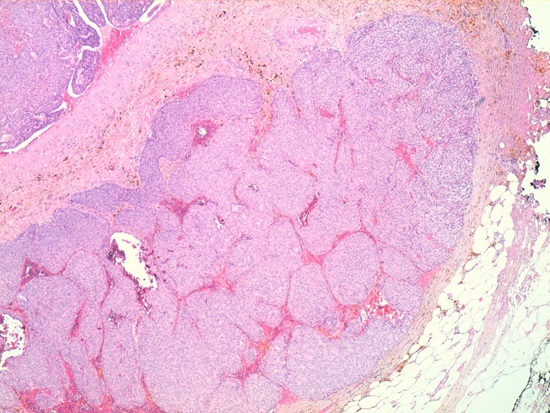

Given these findings the decision to perform a deferred biopsy was reached. An accidental opening of the cyst occurred intra-operatively along with drainage of a bloody fluid. Pathology reported a well-circumscribed, nodular formation in which a solid proliferation of large nests composed of cells with uniform nuclei was observed with low mitotic activity. This formation had a pattern of expansive growth within a partially collapsed cystic cavity and infiltrating area of 10 mm in the wall of the cystic structure. Immunohistochemistry was positive for hormone receptors (estrogen and progesterone), and showed an absence in the expression of HER-2 and p53 negative.

The pathological diagnosis was of a solid papillary intracystic carcinoma with a point of invasion - infiltrating papillary carcinoma and intracystic papillary carcinoma (Fig. 4).